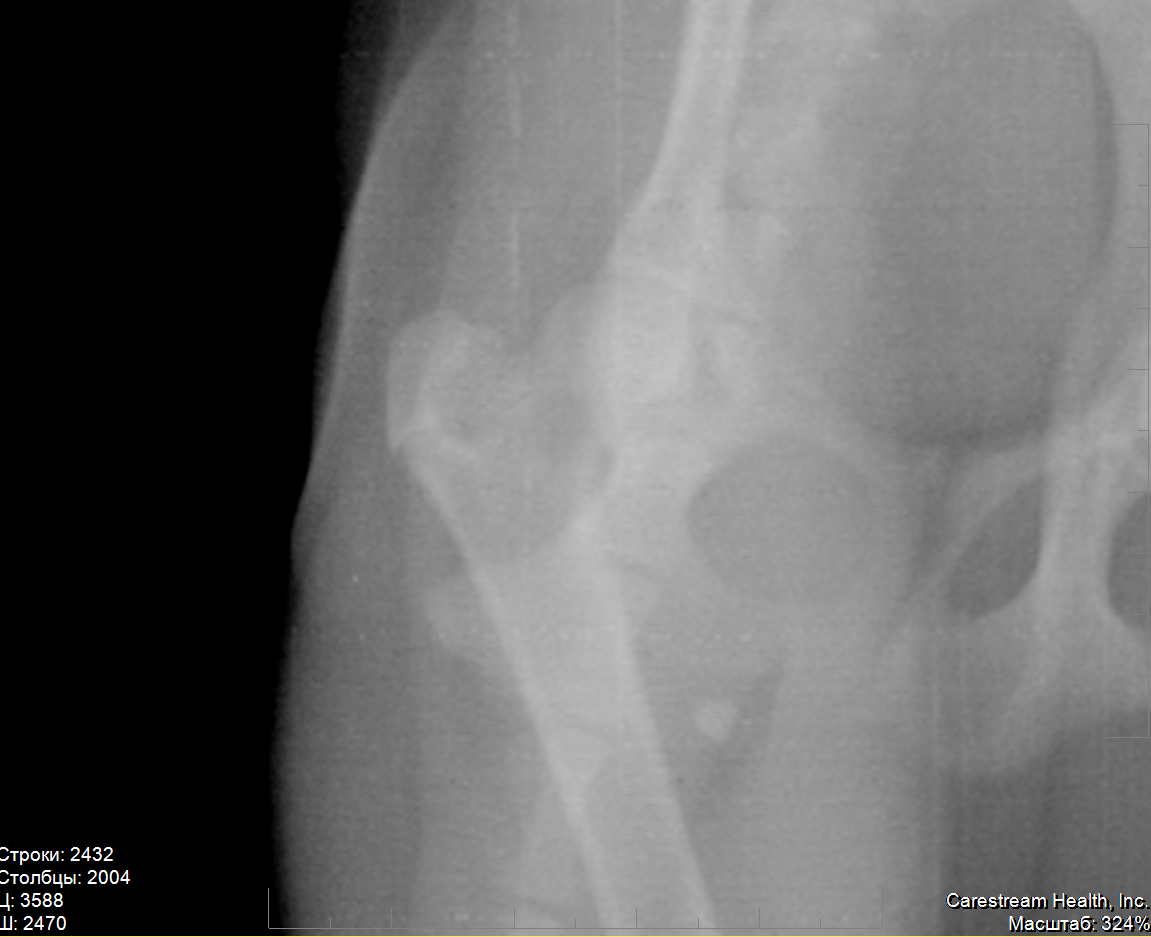

Снимки. Есть диск, но программа на нём почему-то не запускается, если понадобится - разберусь и найду способ открыть.

Мне эти снимки, к сожалению, ничего не говорят :(

Разобрался. Ужасно неудобно пользоваться, и, главное, не знаю, где же нужно увеличивать.

Я своим неопытным взглядом трещины не нахожу :(

вот, попытался увеличить сначала весь тазобедренный, потом правую часть

Вот теперь более-менее понятна картина. По перечисленным симптомам очень похоже на болезнь Пертеса, или остеохондропатию головки бедренной кости. На снимке явно заметна деформация головки правого сустава, левый в порядке: круглый, ровный, гладкий. Трещины на правом не видно, поэтому я бы не стала исключать другой диагноз. Врачу, конечно, виднее, но снимки можно показать и другому специалисту и выслушать его мнение. Пертес часто ошибочно связывают с травматикой, в то время как заболевание имеет наследственный характер и чаще ему подвержены мелкие породы собак. Подробнее - в интернете, а мне больше нечего добавить. Надеюсь, собачка получит своевременную помощь и лечение.

на всякий случай приложу ещё два увеличения

на всех снимках слева - правая нога